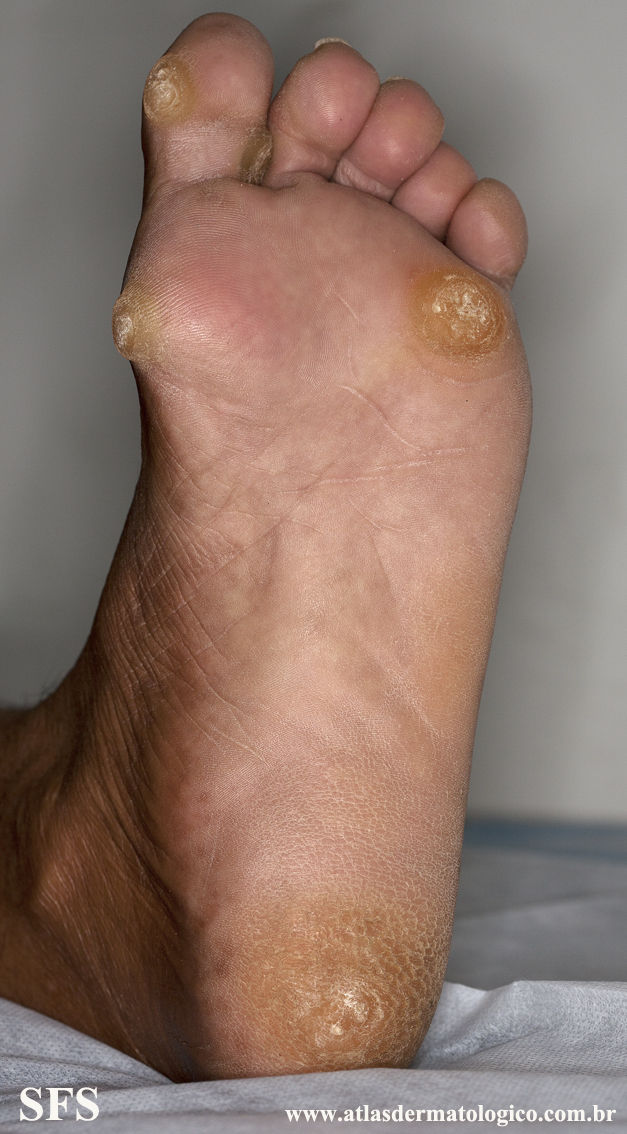

palmoplantar_keratoderma-focal_keratoderma